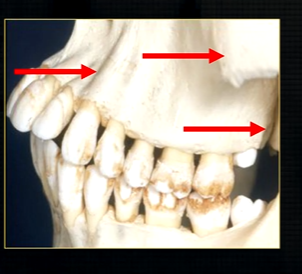

posteriorly, the maxilla….

widens as it articulates with the zygoma or cheekbone

The zygomatic buttress is a key vertical support structure of the midface, formed by the junction of the zygomatic process of the maxilla and the zygomatic bone

bulk/prominence of the zygomatic cheekbone - radiographically this can overly the apical tissues of the upper molar teeth - solid, dense, white shadow

if its hollowed out by the maxillary sinus, it casts a white, radiopaque U shaped shadow - radiolucent centre

the end of the maxilla can be described as,

smooth, rounded end - called the tuberosity

pterygoid hammulus - supports the muscles of the soft palate

coronoid process of the mandible